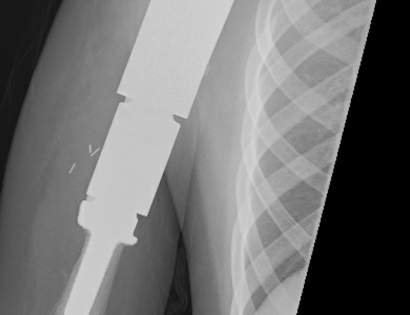

Proximal Humerus X-ray photo

This is an x-ray image of the proximal humerus with the endoprosthesis fully inserted.